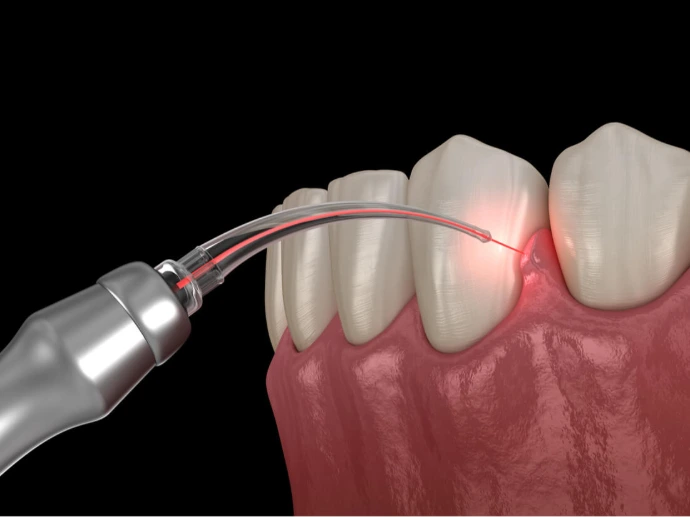

Laser assisted treatments

- LANAP